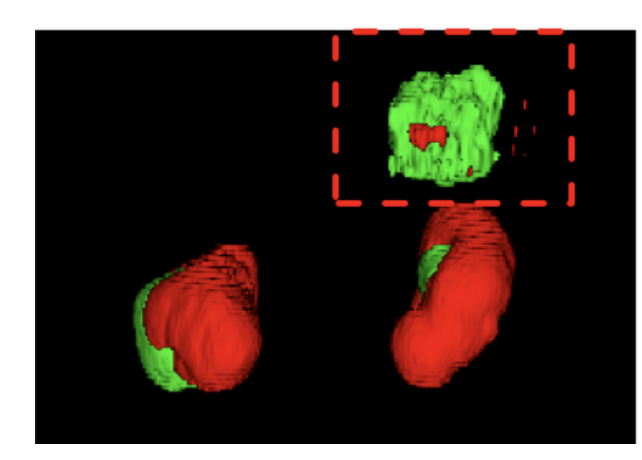

用深度学习方法得到的分割结果,会有一些假阳性区域。通过去除这些假阳性区域,可以提高分割结果。

比如说做肾分割,大家都知道,肾只有左右两边有,如果分割结果出现了三个区域,则可以根据常识,去除那个假阳性区域。

用到的方法就是 连通成分分析Connected-Components。

总结:该方法对二维图像去除假阳性区域很好用,但是无法对三维图像进行操作。

2 cc3d 提供的方法

cc3d 提供了二维和三维的方法实现连通成分分析

总结:这种方法较为复杂,但是可以实现 3d 去除假阳性。